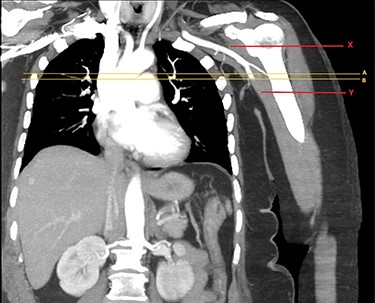

CTA of left upper limb in the coronal plane. X—axillary artery with contrast showing flow as evident in transverse imaging (see Fig. 3), patent in the transverse plane marked A. Flow ceases approximately at the level of the plane marked B. Y—axillary artery occluded as shown with contrast absent.

CTA of left upper limb in the transverse plane. B—axillary artery without contrast showing occlusion due to embolism as evident in transverse imaging at B-line (see Fig. 2).